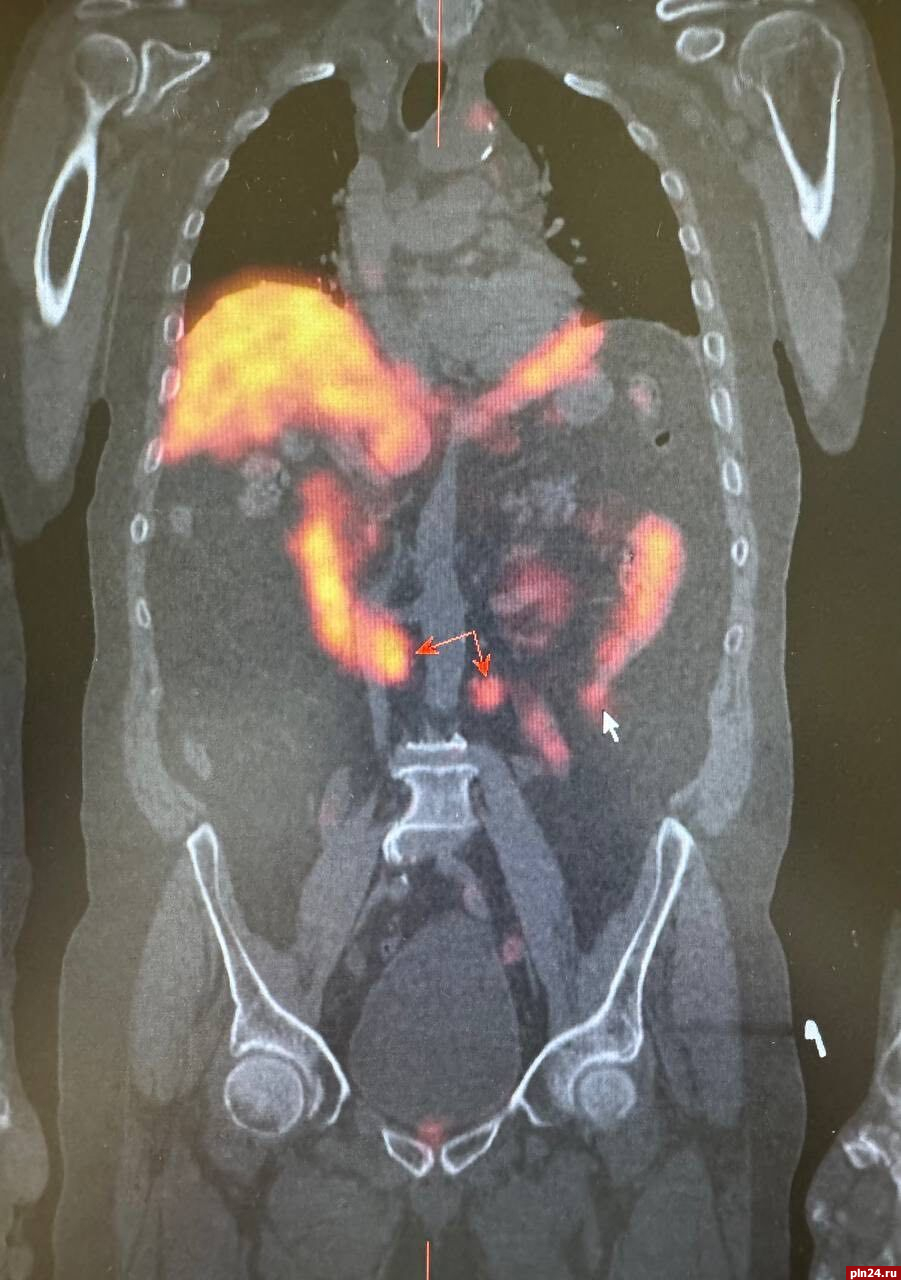

Для уточнения диагноза и получения более детальной информации о состоянии лимфатических узлов была назначена радионуклидная диагностика. Этот метод позволил более точно определить наличие злокачественного опухолевого процесса в предстательной железе, а также подтвердить метастатическое поражение ранее выявленных лимфатических узлов в грудной клетке. Кроме того, радионуклидное исследование показало активное накопление технеция ПСМА в парааортальных лимфатических узлах с обеих сторон.

При этом важно отметить, что на компьютерной томографии не было явных структурных изменений, что затрудняло оценку их состояния и возможности метастазирования, уточнили в министерстве.

Таким образом, результаты радионуклидной диагностики стали решающими в выявлении вторичного поражения лимфатических узлов. Это позволило врачам незамедлительно начать специализированное лечение, что значительно повысило шансы пациента на успешное преодоление заболевания.